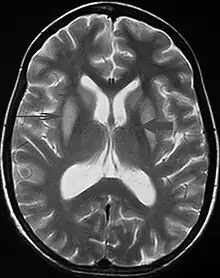

T2 weighted magnetic resonance scan image showing bilaterally symmetrical hyperintensities in caudate nucleus (small, thin arrow), putamen (long arrow), with sparing of globus pallidus (broad arrow), suggestive of extrapontine myelinolysis (osmotic demyelination syndrome)

It can be diagnosed clinically in the appropriate context, but may be difficult to confirm radiologically using conventional imaging techniques. Changes are more prominent on MRI than on CT, but often take days or weeks after acute symptom onset to develop. Imaging by MRI typically demonstrates areas of hyperintensity on T2-weighted images.[29]